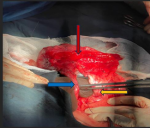

Therapeutic intervention: a percutaneous nephrostomy tube was passed to decompress the abdomen initially. Together with continuous intravenous hydration, a total of 6 L was drained over the first 24 hours of admission. Subsequently, the patient was prepared for a nephrectomy, and the findings, as seen in Figure 2 below, were: 1) left double moiety kidney: with the upper moiety´s ureters inserting into the region of the left suprarenal gland. The lower moiety was blind ending at the UPJ; 2) sac-like left kidney, non-functional, which was removed; 3) left lower moiety ureter ending blindly in the renal pelvis, suggestive of complete UPJ-Obstruction.

Figure 2: kidney showing upper moiety ureter insertion in the adrenal gland and lower moiety ureter draining into the bladder with UPJ obstruction; the red arrow shows the kidney, the yellow arrow shows the dilated lower moiety ureter, and the blue arrow shows the upper moiety ureter inserting into the adrenal gland